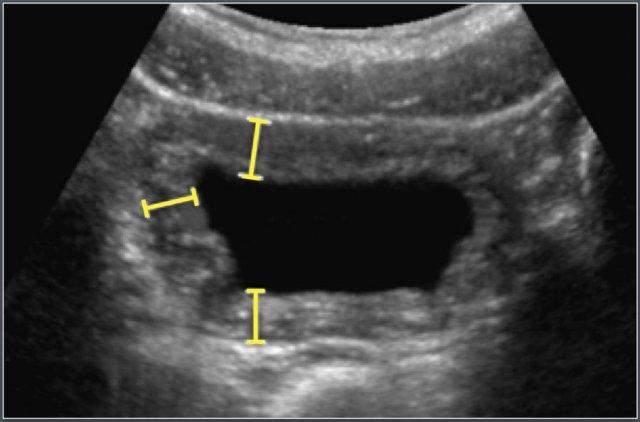

Kỹ thuật Đo lường

Thành bàng quang được đánh giá trên hình ảnh mặt cắt ngang phóng to của bàng quang sau khi đã tiểu hết.

Các phép đo được thực hiện tại ba vị trí:

- Thành trước bên

- Thành bên

- Thành sau bên

Giá trị trung bình của ba phép đo này được sử dụng để phân tích.

Chỉ số Độ dày Thành – Thể tích Bàng quang (BVWTI)

Độ dày thành bàng quang phụ thuộc vào mức độ đổ đầy và dung tích bàng quang.

Do đó, giá trị này được biểu thị thông qua Chỉ số Độ dày Thành – Thể tích Bàng quang (BVWI).

Chỉ số này giúp chuẩn hóa các phép đo thành bàng quang ở các mức độ căng giãn khác nhau và cải thiện độ chính xác chẩn đoán các bất thường đường tiết niệu dưới, đặc biệt ở trẻ em.